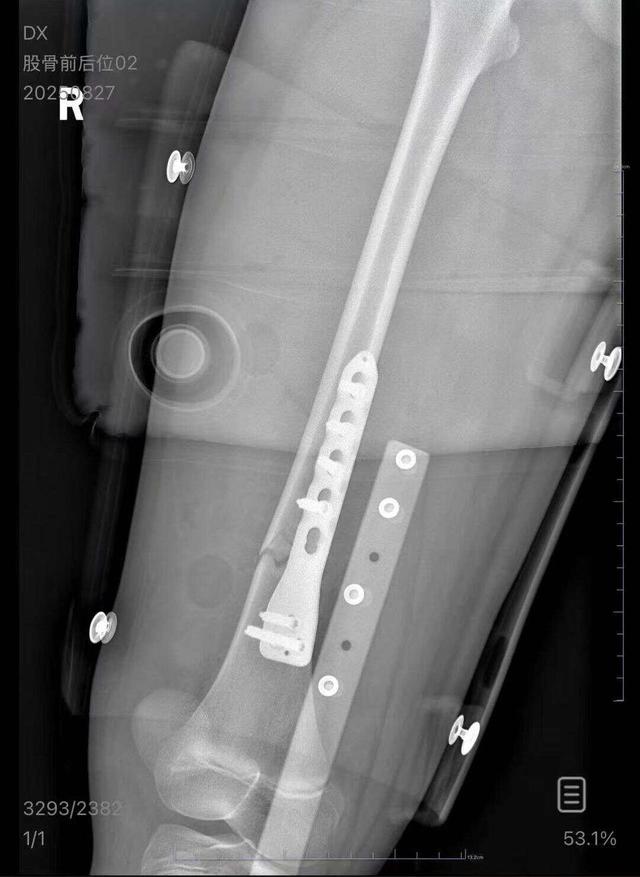

朱女士向记者出示的医院病历显示,8月24日凌晨,朱女士的女儿到医院就诊。医院诊断朱女士的女儿右股骨骨折,需要住院进一步治疗。